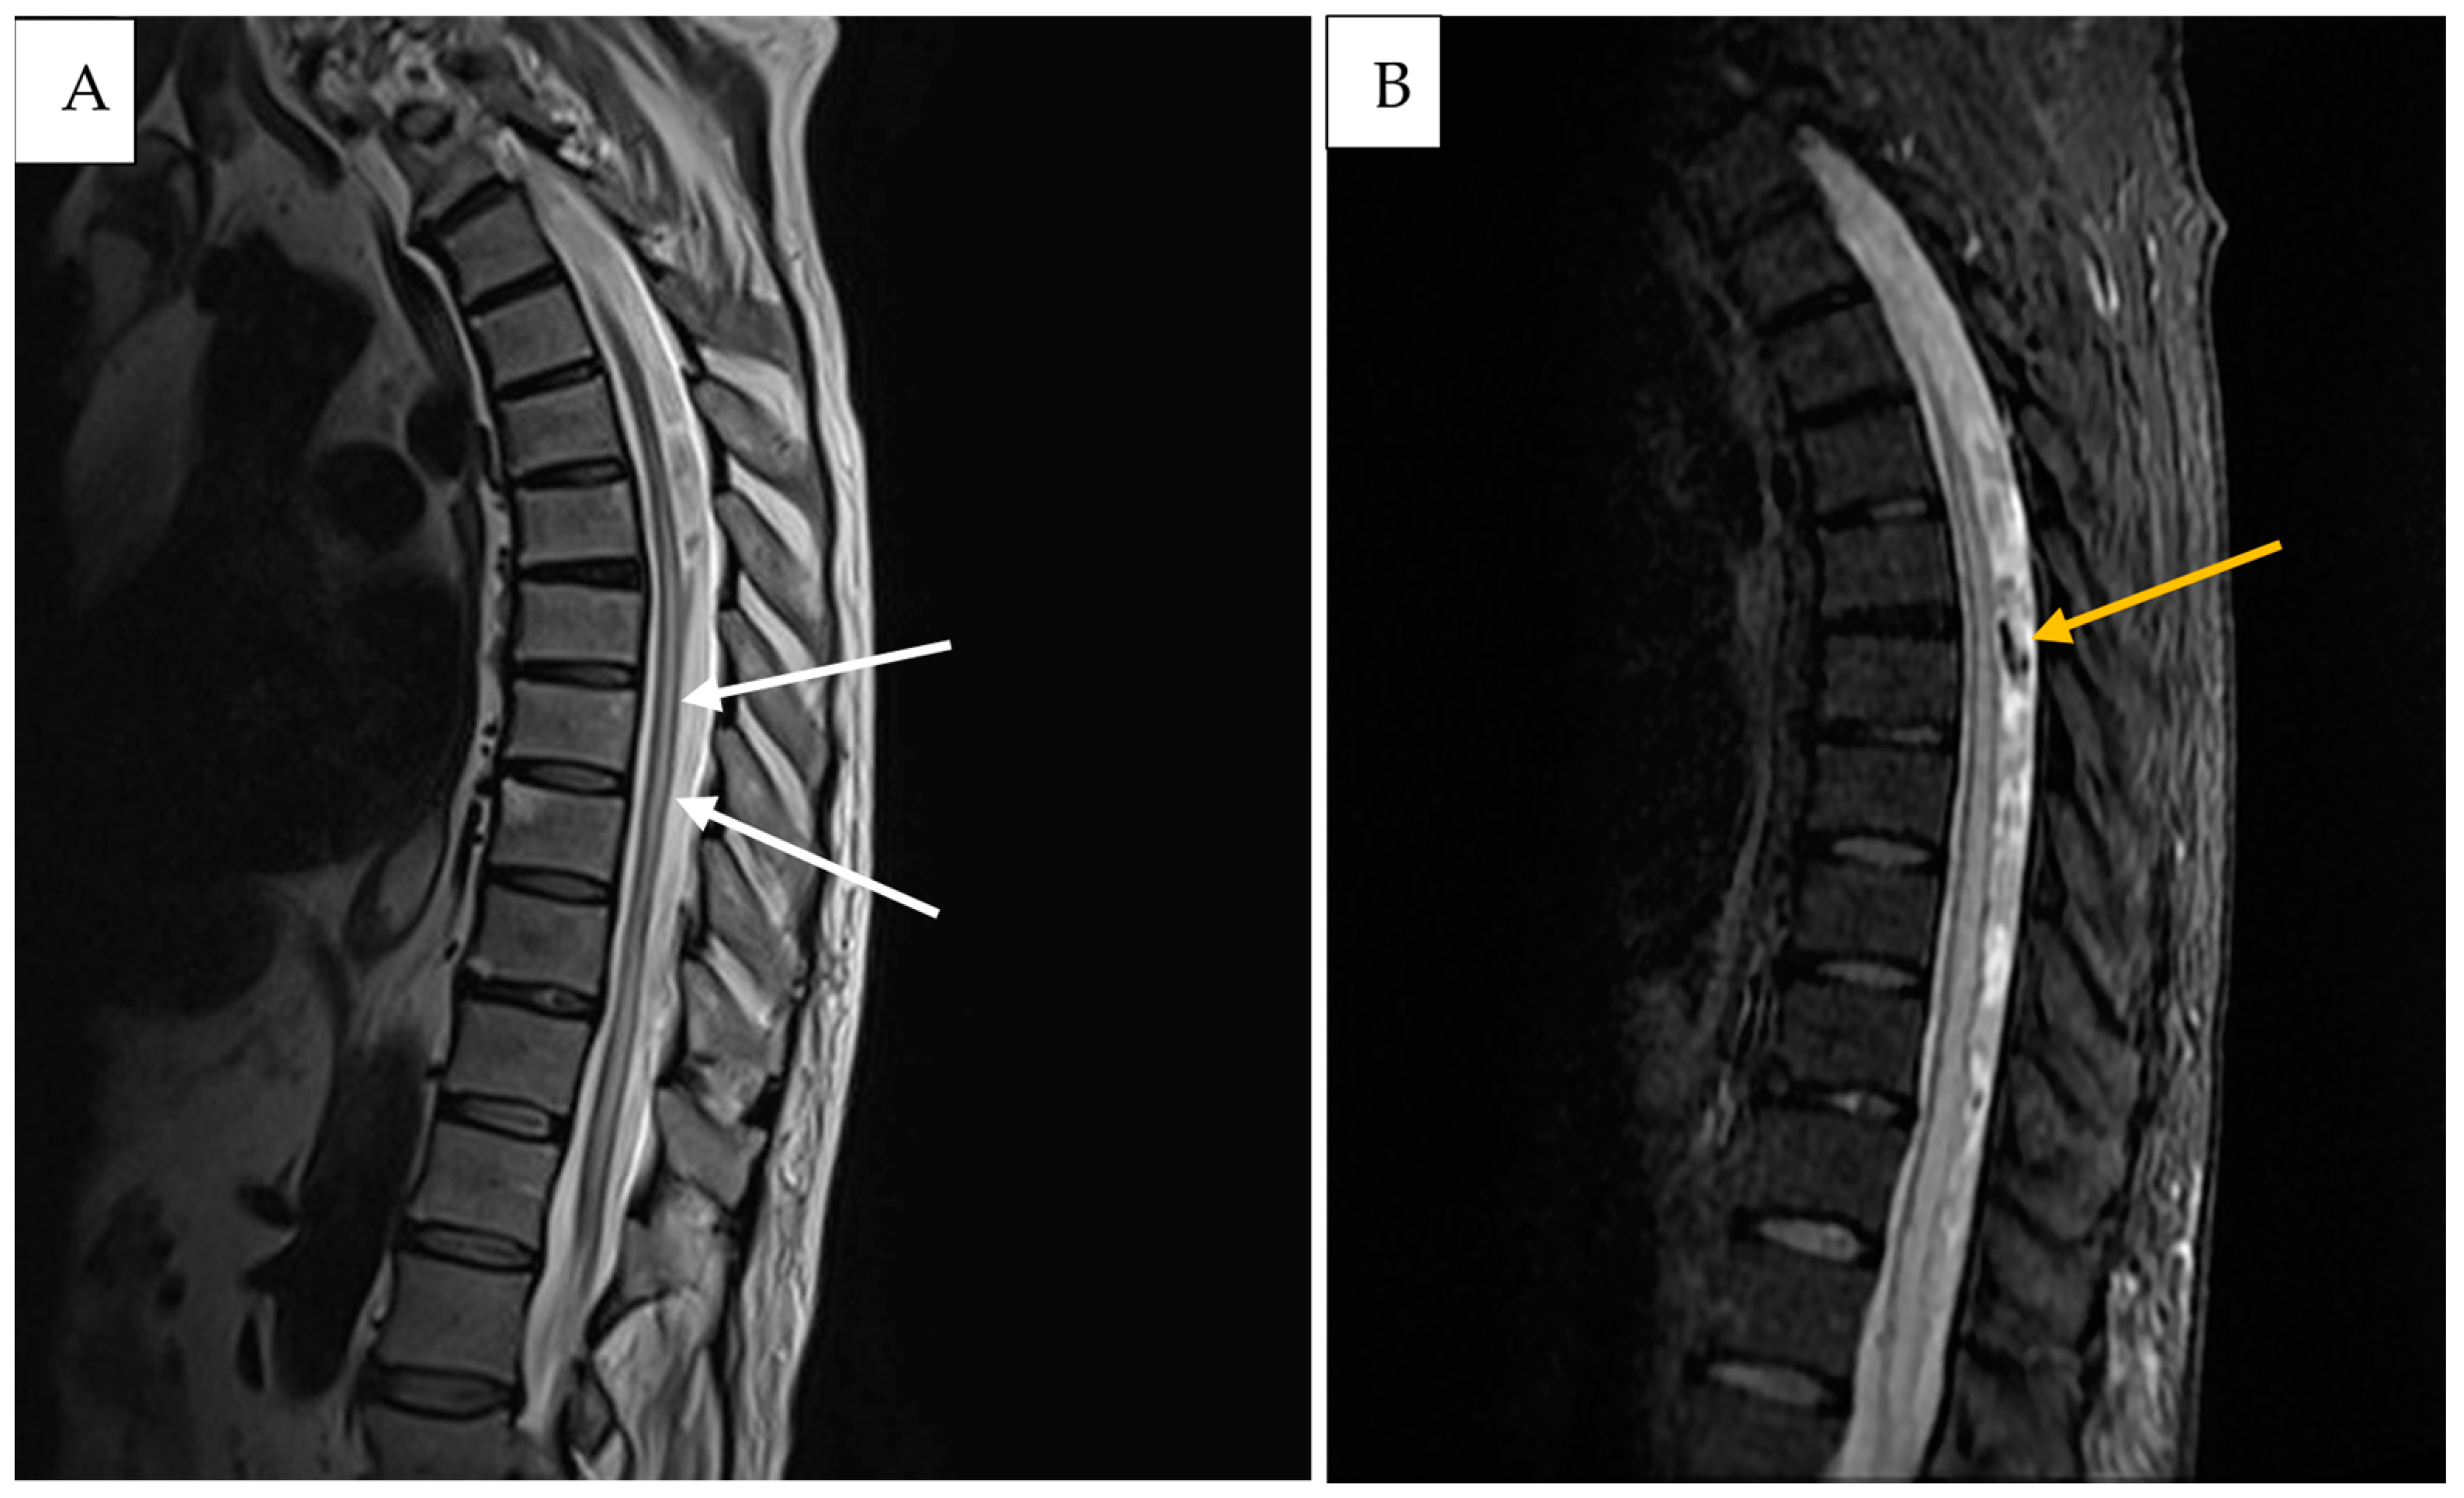

2. Detailed Case Description